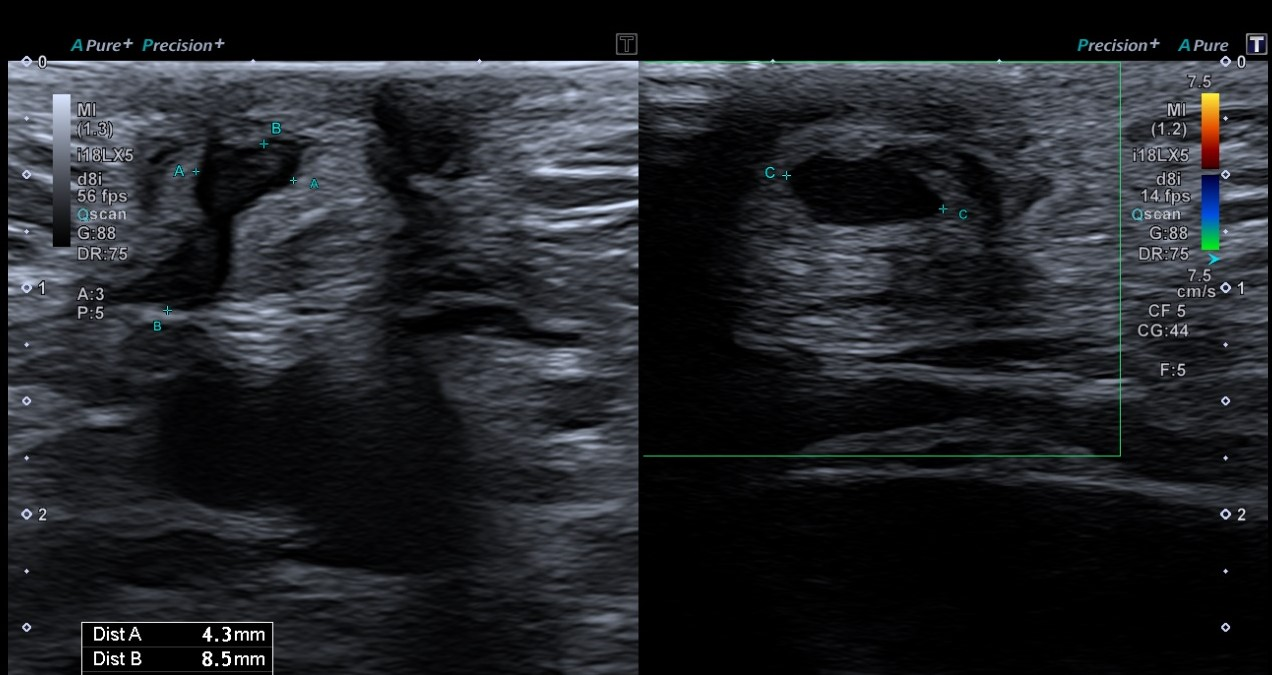

Ecografía partes blandas: En localización infraumbilical, sin aparente dependencia de estructuras profundas ni modificación en maniobra de Valsalva, lesión hipoecoica bilobulada (4,3 x 8,5 x 7,1 mm) con aparente conexión hacia región vesical, sobre la que no se demuestra vascularización, inespecífica, que podría corresponder a seno uracal, sin poder descartar sobreinfección asociada.